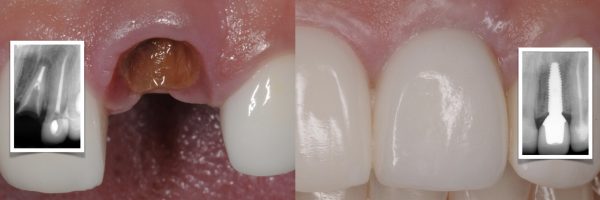

2-day basic implant placement course + marketing module combo